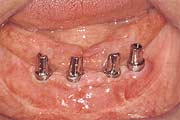

Zahnloser Kiefer

Viele Prothesenträger klagen über den schlechten Sitz und

schmerzhaften Druckstellen. Haftmittel oder mechanische Hilfen lösen

diese Probleme nicht dauerhaft und zufriedenstellend.

Implantate können Abhilfe schaffen, abhängig von Ihren Voraussetzungen und Wünschen. So kann der Tragekomfort mit der Anzahl der Implantate erheblich gesteigert werden, bis hin zu einer rein auf künstlichen Wurzeln getragenen Prothese.

Beim CAMLOG(r) -System stehen unterschiedliche Möglichkeiten für Sie zur Verfügung:

Druck-Knopf-Verankerung - einfach und zuverlässig

![]() |